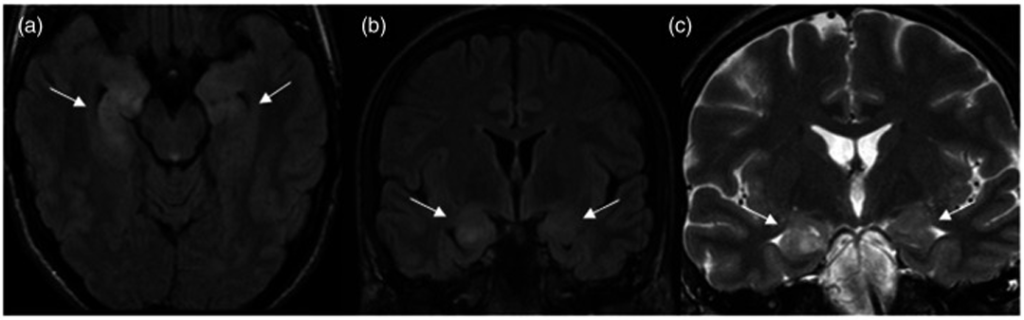

La resonancia magnética cerebral (functional magnetic resonance imaging, MRI; en inglés) mostró focos hiperintensos en el eslenio del cuerpo calloso. A la mañana siguiente, se produjo una nueva convulsión epiléptica con paro respiratorio.

El paciente fue trasladado a la unidad de neurología y se realizó otra resonancia magnética que demostró una hiperintensidad de la señal en el hipocampo.

La resonancia magnética cerebral reveló signos de hiperintensidad en el hipocampo (bilateralmente) y la amígdala, así como en el núcleo pulvinar izquierdo (áreas cerebrales que se ocupan de las emociones, memoria y comportamiento social, entre otros), sin mejora. El EEG mostró anomalías bilaterales generalizadas graves y actividad de onda lenta que involucraba a los lóbulos temporales.